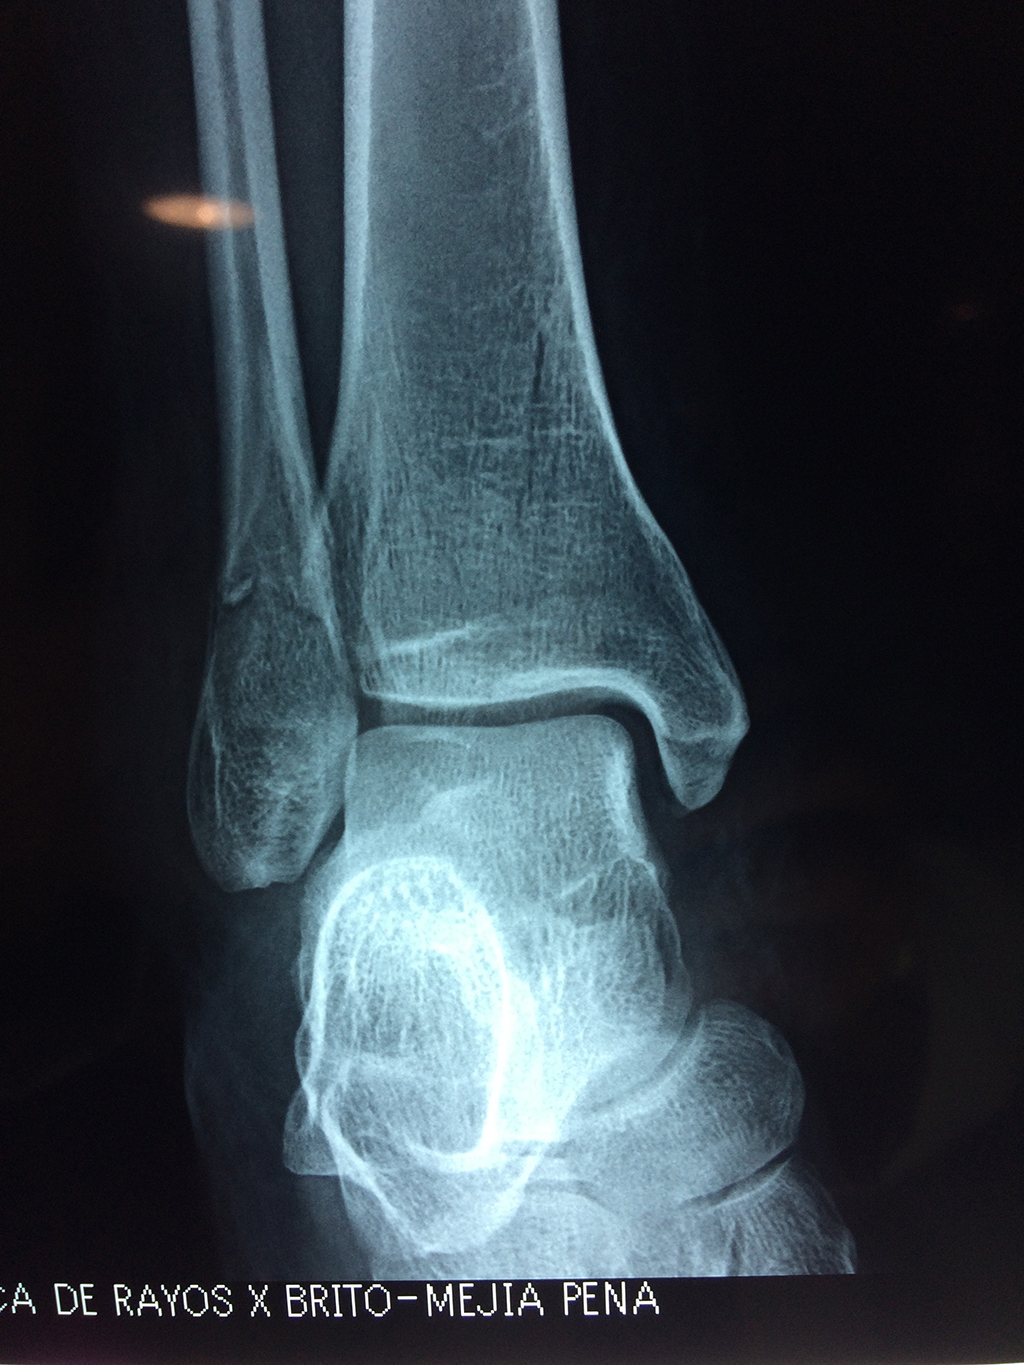

Una fractura de tobillo es la rotura de uno o más de los huesos del tobillo. Estas fracturas pueden ser:

- La fractura se extiende hasta la articulación del tobillo (fractura intra-articular).